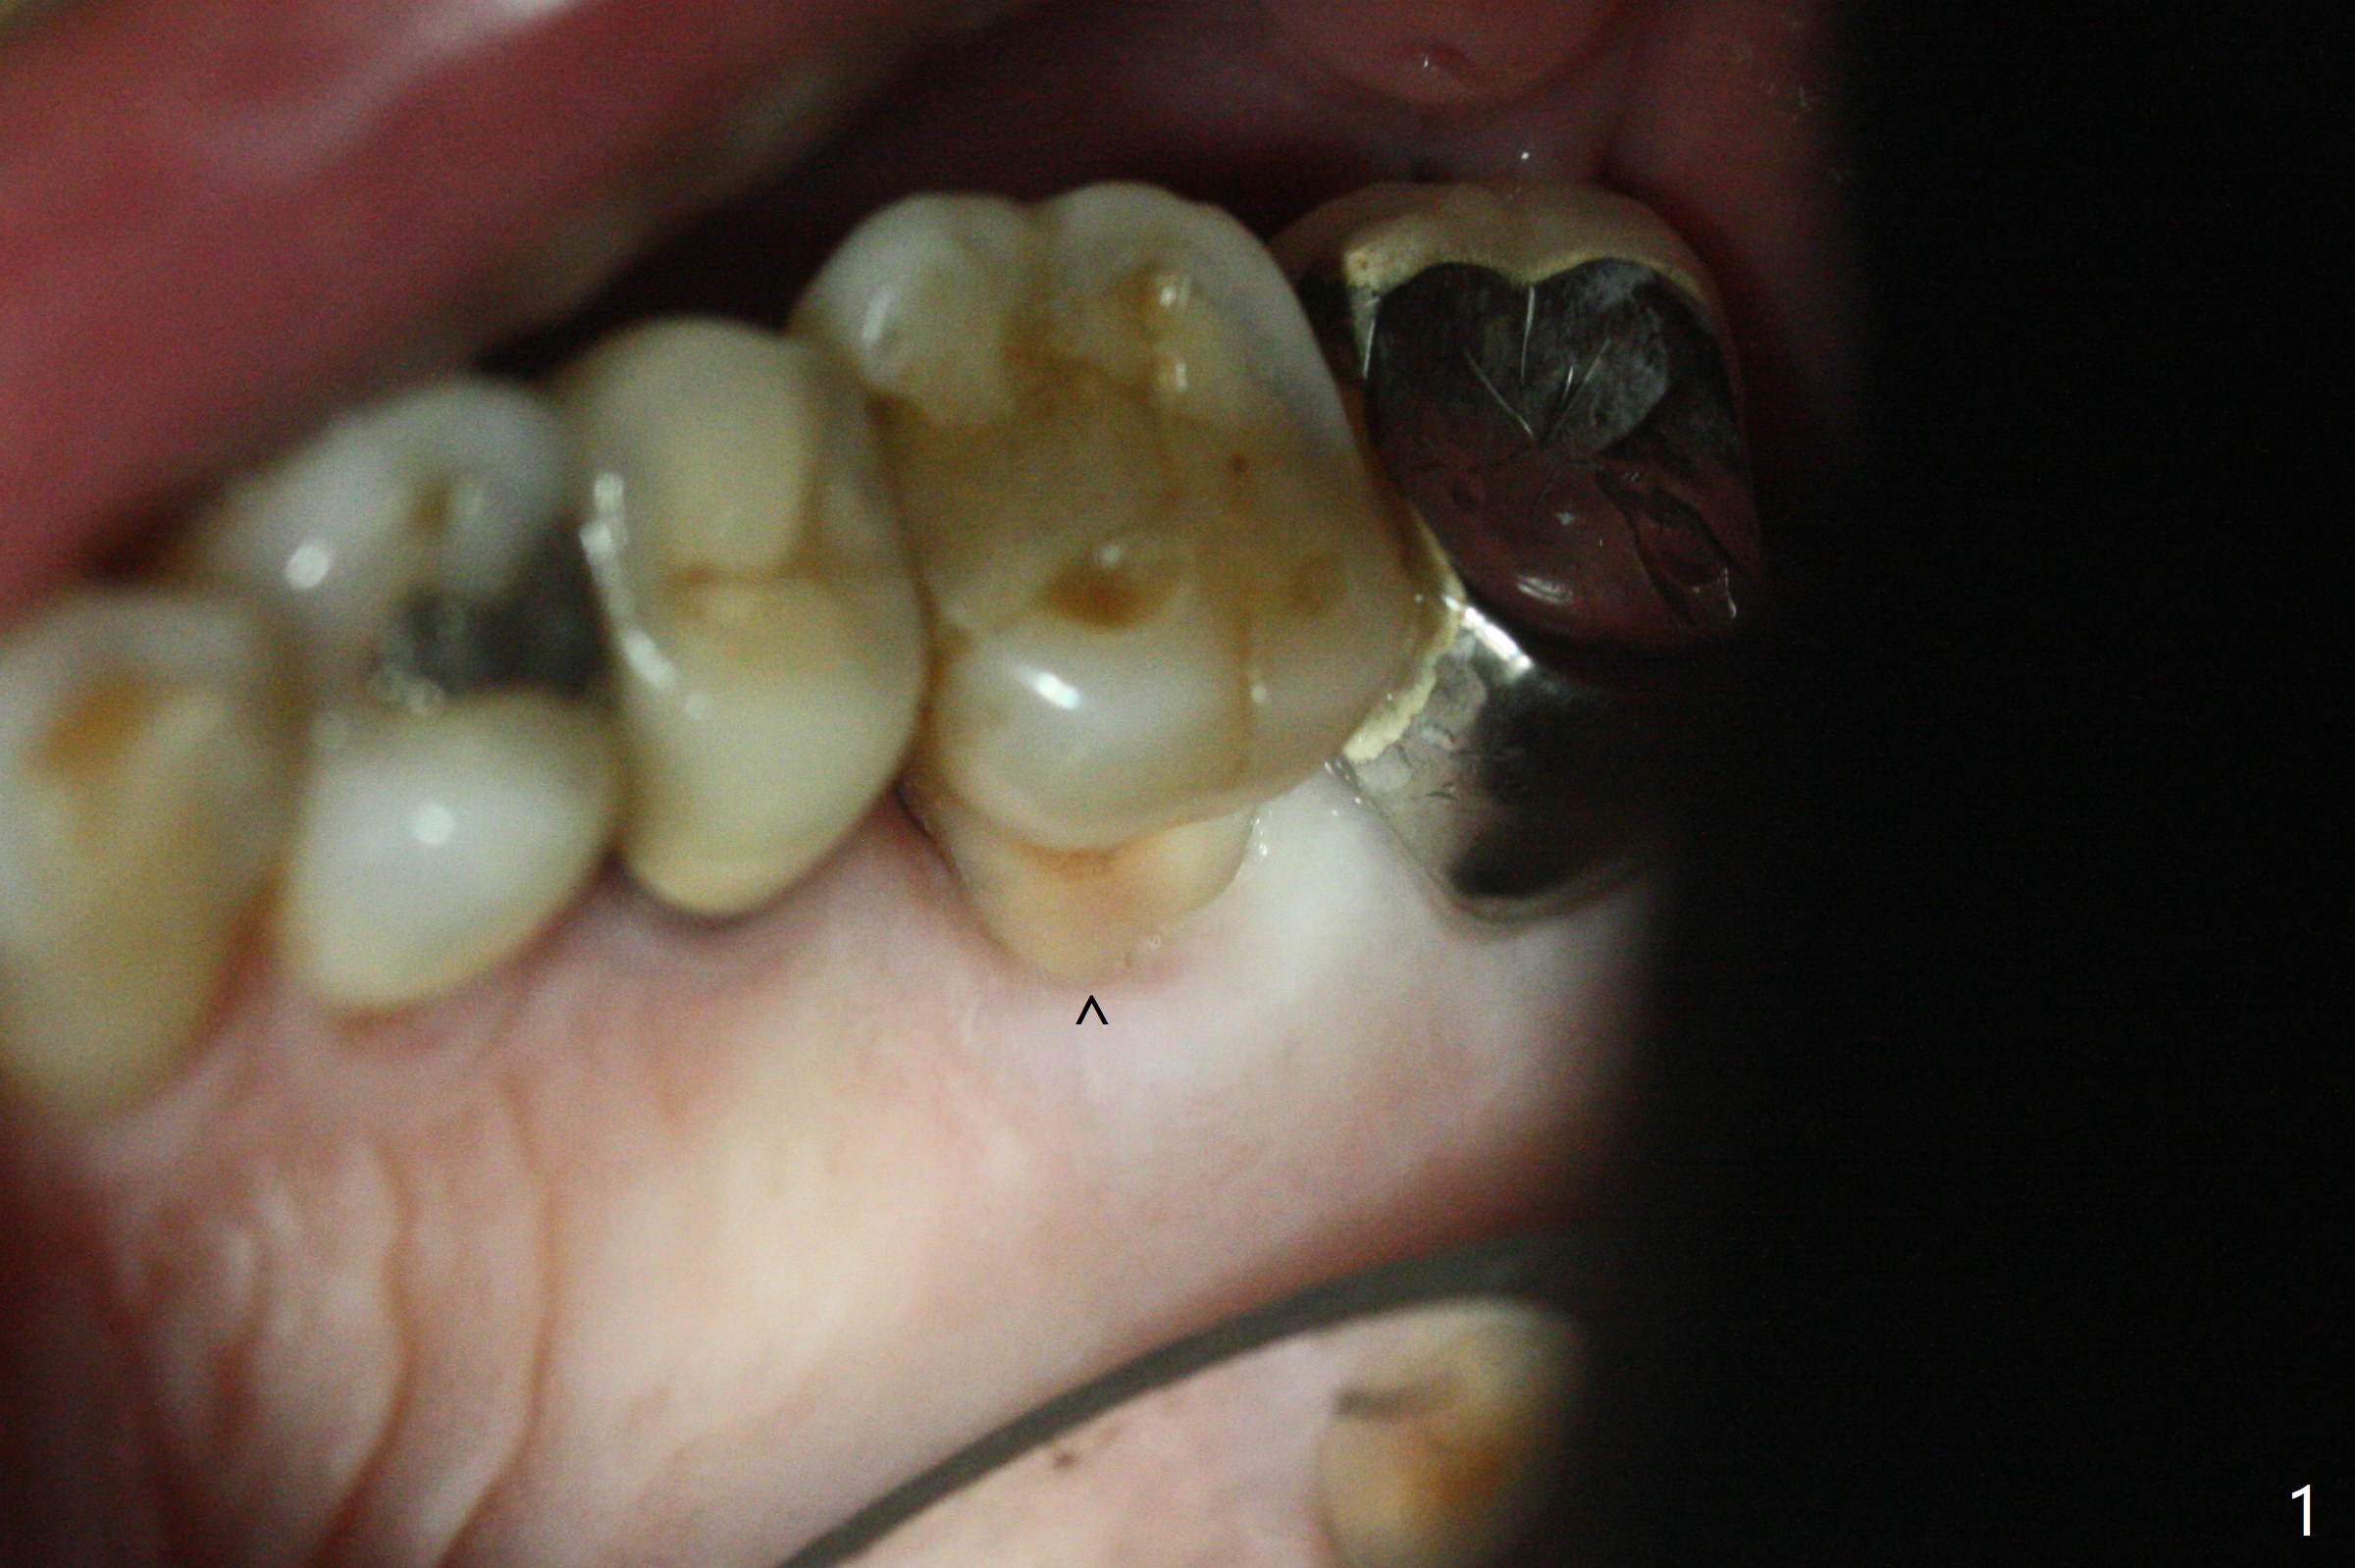

左上6腭侧退缩牙龈(图一:箭头)深部没有骨壁(图二:*),4.5x11毫米植体周围缺损(图三:*)由粘性骨粉(皮质骨,图四:*)填入,即刻临时牙冠(图五:P)覆盖腭侧缺损(空箭头)和PRF膜。临时牙冠颊腭侧做的很宽(图六),目的是关闭腭侧缺损,术后四周在不影响骨粉覆盖情况下,牙冠腭侧适当向颊侧缩小(图七:箭头),但是不应该缩短龈下边缘。术后四个月骨粉形态接近原位骨(图八),但是腭侧软硬组织仍有缺损,炎症。